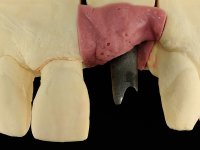

I’ve decided to rehabilitate the dental implant by closely mimetizing the crown and the root of the adjacent teeth, as well as the gingiva close to the soft tissue deformity. Thus, the prosthetic component would integrate three parts: crown, root and gingiva.

The angulation of the dental implant did not allow for a screwed prosthesis. Thus, an anatomical abutment was used and the crown margin was milled 1mm infragingival, to allow the removal of the cement. The prosthetic component included a ceramic part emulating the crown and the root of the adjacent teeth, and a gingival part to compensate the soft tissue deficiency. Periodontal surgery to regenerate soft tissue in a vertical deficiency is complex and unpredictable, hence this prosthetic option. Although unconventional, this rehabilitation was well accepted by the patient, easy to perform and proved to be aesthetically satisfying and stable over time.